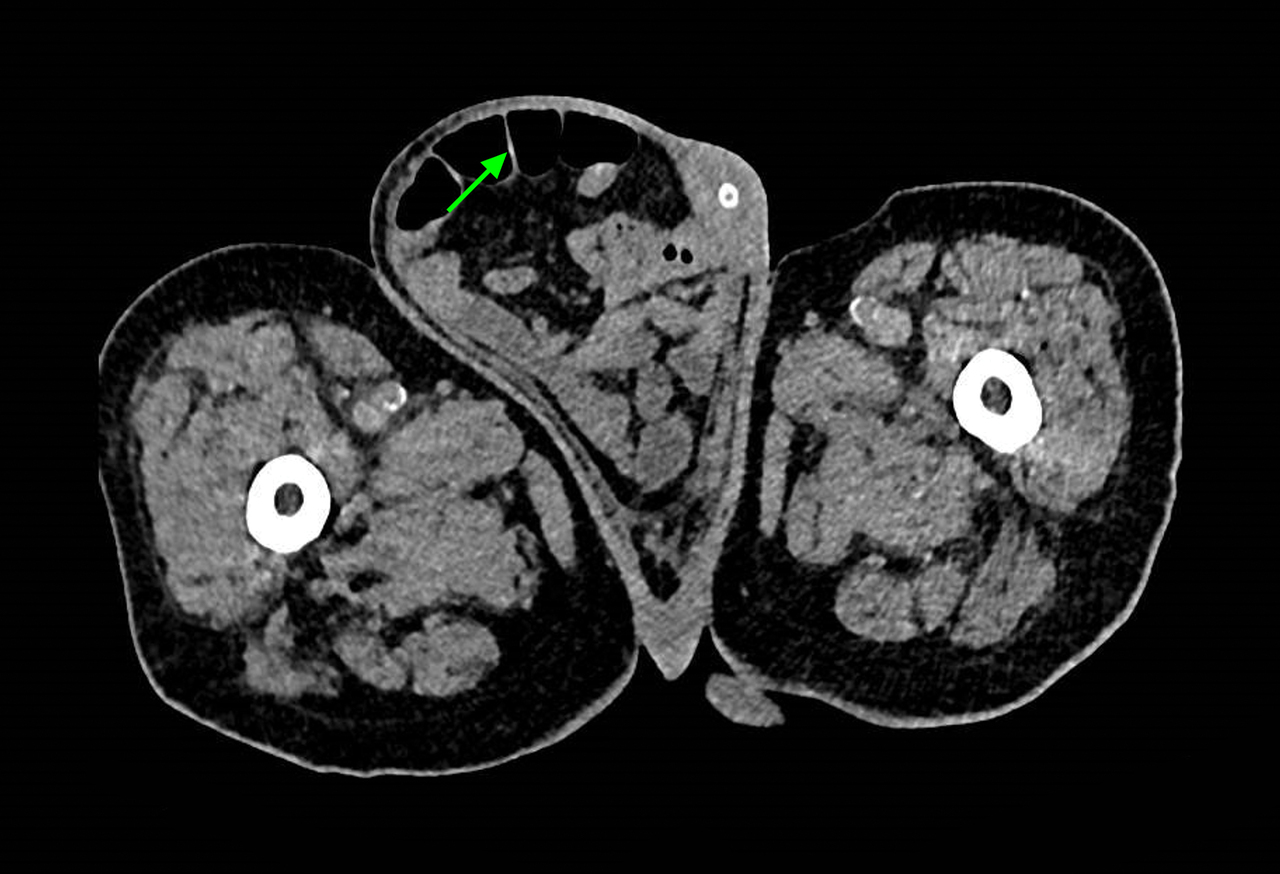

Le scanner montre une volumineuse hernie inguinale avec des anses digestives (flèche). Cette hernie inguinale a entraîné des épisodes subocclusifs responsables de vomissements, à l’origine des pneumopathies d’inhalation.